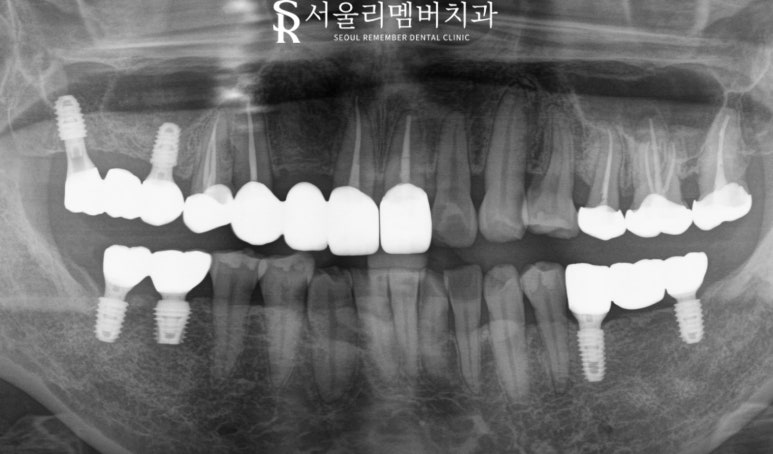

엑스레이로 사진을 찍어 확인해 보니

전체적으로 치조골 퇴축되어 있고

특히 10번 대 보철 치료한 곳은

더 심하게 뼈가 내려가 있어

핀셋으로 살짝 흔들어보아도

동요가 느껴질 정도로 흔들림이

크게 느껴졌습니다.

오래된 보철과 잇몸 사이의

공간이 만들어지면서 식편압입이 생기고

이에 따라 치주염이 발생하면서

흔들리기 시작한거라고 판단합니다.

#15,17,35,37,46,47 은 임플란트

#11,13,14,25,26,27은 신경치료로

아픈 구강 해결해 드리기로 했습니다.

뼈가 많이 퇴축되었는데 괜찮나요?

임플란트 픽스처가 들어가려면

충분한 골량이 있어야 됩니다.

뼈이식과 가이드 임플란트를

통해 안전하게 계획을 세웠습니다.